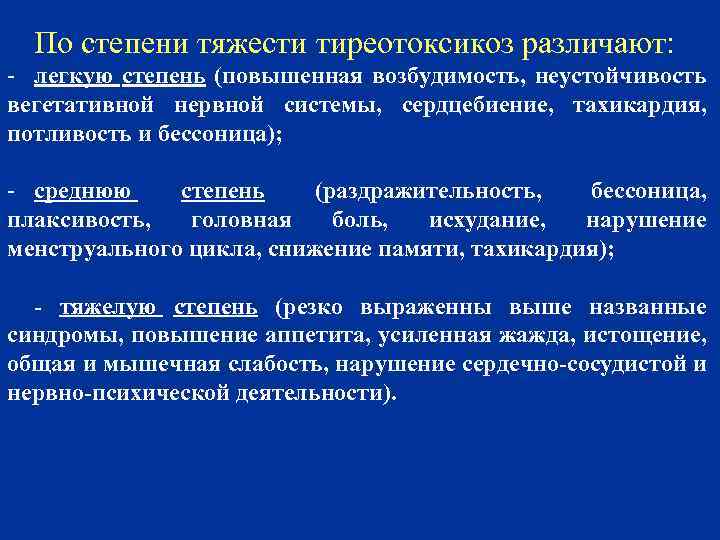

По степени тяжести тиреотоксикоз различают: - легкую степень (повышенная возбудимость, неустойчивость вегетативной нервной системы, сердцебиение, тахикардия, потливость и бессоница); - среднюю степень (раздражительность, бессоница, плаксивость, головная боль, исхудание, нарушение менструального цикла, снижение памяти, тахикардия); - тяжелую степень (резко выраженны выше названные синдромы, повышение аппетита, усиленная жажда, истощение, общая и мышечная слабость, нарушение сердечно-сосудистой и нервно-психической деятельности).

По степени тяжести тиреотоксикоз различают: - легкую степень (повышенная возбудимость, неустойчивость вегетативной нервной системы, сердцебиение, тахикардия, потливость и бессоница); - среднюю степень (раздражительность, бессоница, плаксивость, головная боль, исхудание, нарушение менструального цикла, снижение памяти, тахикардия); - тяжелую степень (резко выраженны выше названные синдромы, повышение аппетита, усиленная жажда, истощение, общая и мышечная слабость, нарушение сердечно-сосудистой и нервно-психической деятельности).